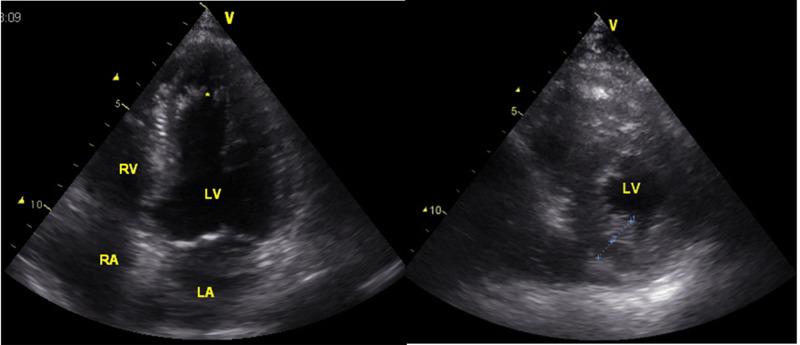

The patient is a 55-year-old male in whom MID was diagnosed at age 34 upon clinical presentation, muscle biopsy, and biochemical investigations. Phenotypically, he manifested with multisystem disease including the brain (mental retardation, epilepsy, sleep disorder, cerebellar atrophy), eyes (cataract, myopia), ears (hypoacusis), heart (hypertrophic, cardiomyopathy, QT-prolongation, left anterior hemiblock, noncompaction), intestines (hepatopathy, cholecystolithiasis), muscle (myopathy), peripheral nerves (neuropathy), and the bone marrow (anemia). Additionally, there was facial dysmorphism (upslanting palpebral fissures, hypertelorism, protruding bulbs) and multiple orthopedic abnormalities, including camptocormia in the absence of axial myopathy, barrel thorax, gibbus, genu valga, knee contractures, bilateral gonarthrosis, bilateral ankle arthroses, and outwardly rotated feet. These abnormalities were complicated by wedge vortex, vertebral stenosis, and coxarthrosis requiring right hip endoprosthesis. His mother manifested with a largely different phenotype.

该患者为一名55岁男性,34岁时因临床表现、肌肉活检及生化检查被诊断为MID。表型上,他表现为多系统疾病,包括脑部(智力发育迟缓、癫痫、睡眠障碍、小脑萎缩)、眼睛(白内障、近视)、耳朵(听力减退)、心脏(肥厚型心肌病、QT间期延长、左前分支阻滞、心肌致密化不全)、肠道(肝病、胆囊结石)、肌肉(肌病)、周围神经(神经病变)及骨髓(贫血)。此外,还有面部畸形(睑裂上斜、眼距增宽、眼球突出)及多种骨科异常,包括无轴性肌病的脊柱前凸、桶状胸、脊柱后凸、膝外翻、膝关节挛缩、双侧膝关节炎、双侧踝关节病及足外旋。这些异常因楔状椎体、椎管狭窄及髋关节病而复杂化,需要进行右髋关节置换术。他的母亲表现出的表型则大不相同。